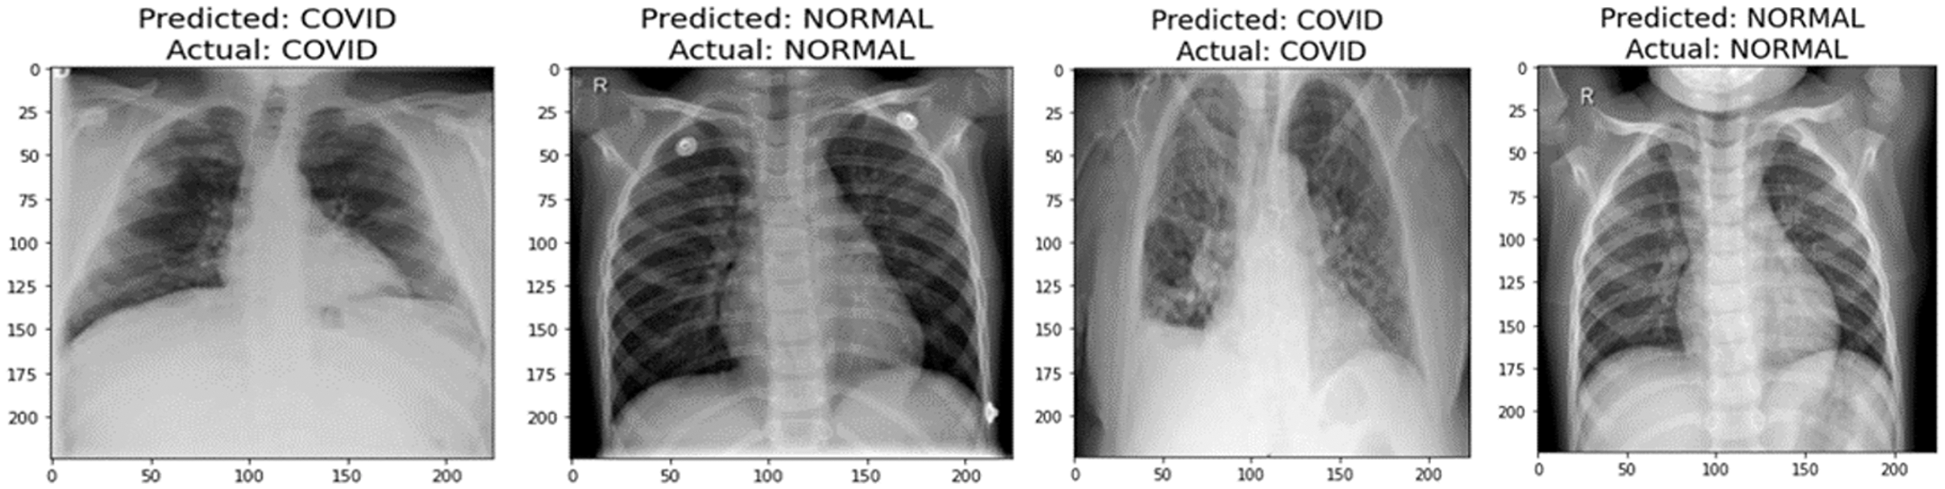

A graphical representation of the accuracy and loss for edge device 1 categorization is shown in Fig. 11, and the following output that it is anticipated to produce is shown in Fig. 12. It was completely accurate in its prediction for all six images, although they were selected at random from the test dataset. The training and testing accuracy, as well as the training and testing loss, for edge device 2 are shown in Figs. 13, and 14, respectively.

Figure 12: Prediction of edge device 1

Figure 14: Prediction of edge device 2